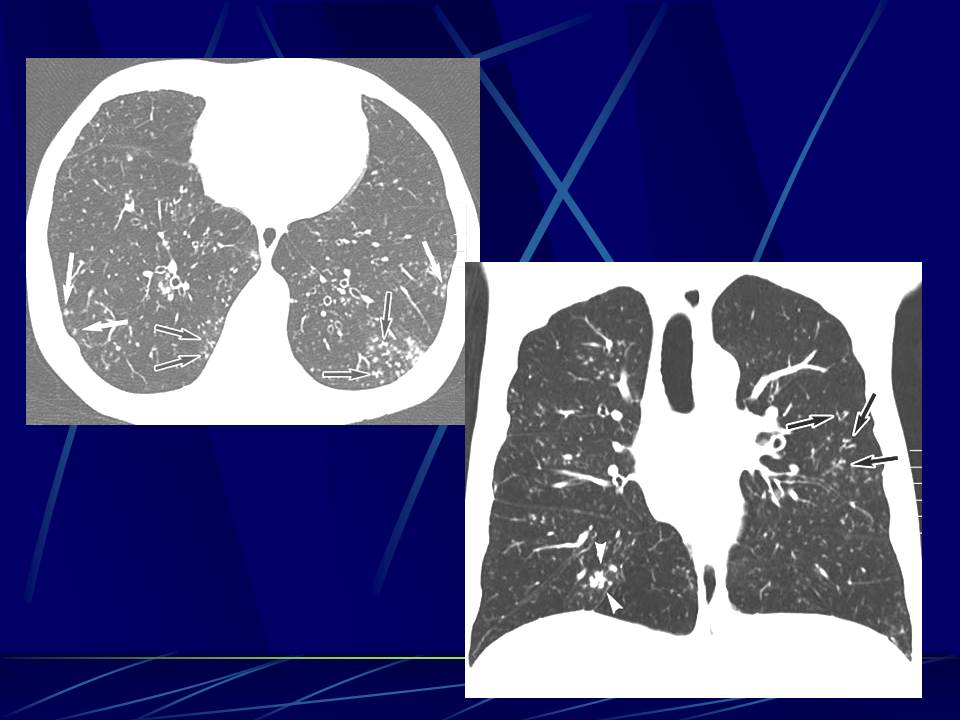

肺部真菌感染影像学分析